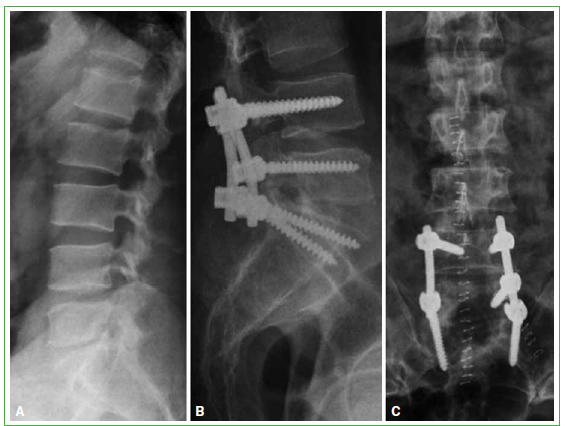

Figura 2.

Tomografía computarizada de columna lumbar. A. Corte lateral. Lesiones líticas en la placa superior y el cuerpo de L3 y L4. B. Corte coronal. Lesiones líticas en la placa superior y el cuerpo de L3 y L4. C. Radiografía de columna lumbar lateral. Se observa el resultado de la instrumentación lumbar larga de T12-L1-L2-L5 y S1, realizada en noviembre de 2012.

En controles seriados, se detecta colapso vertebral de L2, L3 y L4, además de quistes hidatídicos en el músculo psoas ilíaco, por lo que se decide realizar una instrumentación posterior larga. En noviembre de 2012, se procede a una fijación posterior de T12-L5 con tornillos pediculares y a una laminectomía amplia de L3-L4 (Figura 2).

Figura 3.

Resonancia magnética de columna lumbar, cortes coronal y sagital. Se observa compromiso lítico de cuerpos vertebrales L2, L3 y L4. (Octubre de 2015).